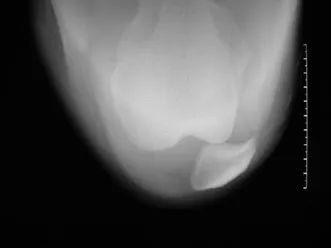

髌骨轴位片